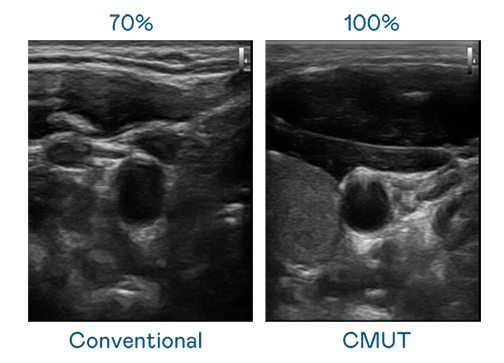

CMUT 技術是一種用電容式微機電元件來產生超音波訊號的技術。與傳統 PZT 壓電式技術相比,CMUT 頻寬增加 30%,更寬頻的超音波訊號讓影像解析度大幅提升,是實現高影像品質醫療超音波掃描、促進精準醫療發展的關鍵技術。

大頻寬帶來超清晰影像

超音波影像的解析度高低,首先取決於探頭能發出的訊號頻寬。爱游戏体育网页登录 CMUT 可提供高清晰的超音波訊號,提供高頻寬、高靈敏度、影像紋理細節更高的超音波影像,協助醫護人員縮短影像判讀時間及利用精準的醫療影像進行診斷。